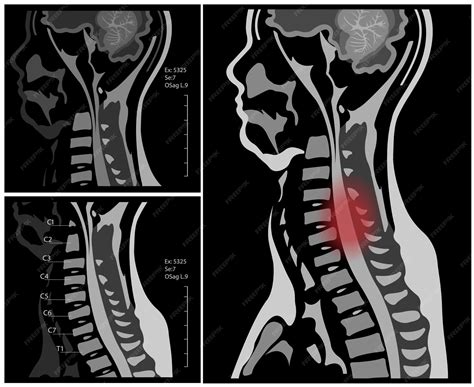

Your cervical spine is the first seven stacked vertebral bones of your spine. This region is more commonly called your neck. The cervical spine has 7 stacked bones called vertebrae, labeled C1 through C7. The top of the cervical spine connects to the skull, and the bottom connects to the upper back at about shoulder level. Sep 27, 2024 · The cervical spine consists of seven vertebrae and acts as bony protection for the spinal cord. This is important because injuries to the spinal cord can be devastating and result in disability. Nov 10, 2025 · Cervical has many uses in medical terminology and can apply to the neck, the cervix, and sometimes to other neck-like structures. Learn what it means. Cervical pain, also known as neck pain, is a common condition that affects many individuals. It refers to discomfort or soreness in the neck area, usually caused by muscle strain, poor posture, injury, or.

The cervical spine has a lordotic curve (a backward C-shape) - just like the lumbar spine. The cervical spine is much more mobile than both of the other spinal regions - think about all the directions and. An expert understanding of cervical anatomy is critical to physiotherapists working in this region. An understanding of this anatomy is essential for assessment and treatment of cervical spine problems. Nov 29, 2025 · The cervical spine, commonly known as the neck, is the uppermost segment of the vertebral column. It functions as the flexible connection between the head and the rest of the body. Apr 5, 2024 · Learn about cervical spine anatomy, diseases and conditions which may affect the cervical spine and what treatments neurosurgeons can provide.